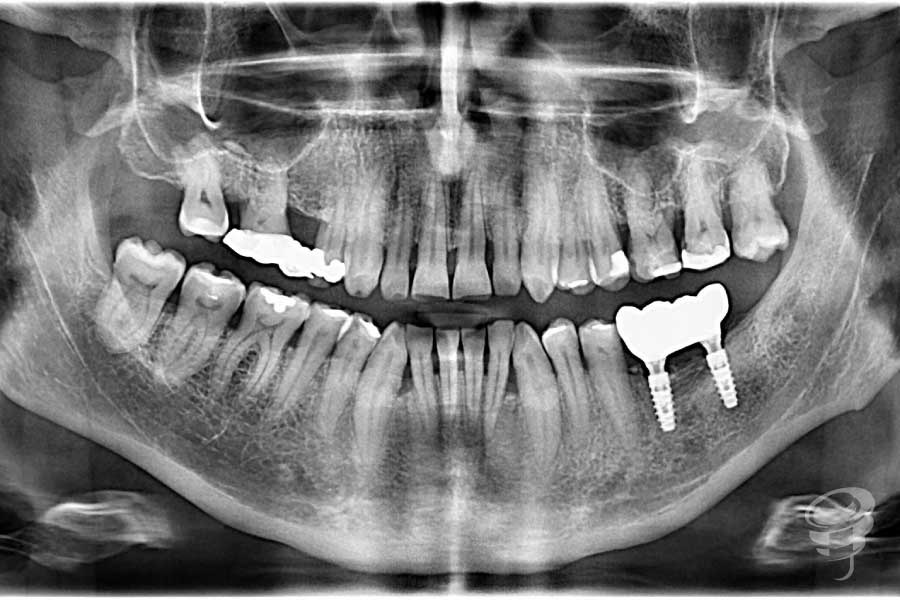

Cirugía de colocación de 2 implantes en posiciones 36 y 37. Se retiran también los tornillos de fijación de las láminas óseas y se realiza una radiografía periapical de control postoperatorio.

Figura 12 (A, B, C, D, E y F)